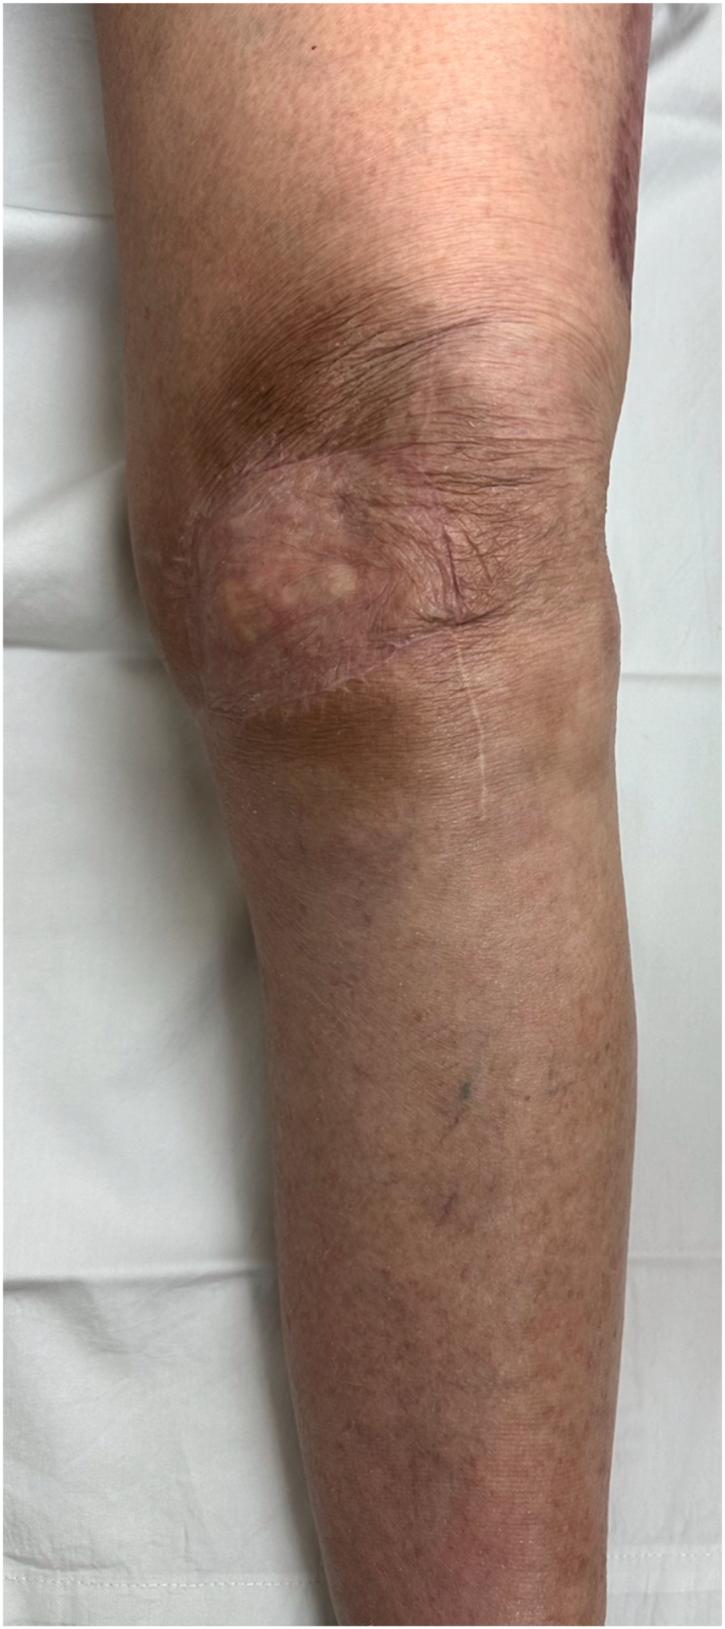

激光辅助吲哚菁绿血管造影术作为复杂关节置换软组织管理决策的临床辅助手段

Laser-Assisted Indocyanine Green Angiography as a Clinical Adjunct for Complex Arthroplasty Soft Tissue Management Decisions.

Soft tissue management is critical to successful perioperative management of total joint arthroplasty patients. Patient medical and surgical history can significantly complicate the soft tissue envelope of a patient undergoing primary or revision arthroplasty. Here we present 2 cases demonstrating the use of Laser-Assisted Indocyanine Green Angiography in evaluating tissue perfusion perioperatively. The information obtained with Laser-Assisted Indocyanine Green Angiography serves as a valuable clinical adjunct for surgeon decision making for total joint arthroplasty soft tissue coverage. This report demonstrates the clinical value of this underutilized tool, in an effort to highlight its effectiveness and potential uses for arthroplasty surgeons.

摘要

软组织管理对于全关节置换患者的围手术期成功管理至关重要。患者的内科和外科病史会显著增加初次或翻修关节置换患者软组织包膜的复杂性。在此,我们展示2例病例,说明激光辅助吲哚菁绿血管造影术在围手术期评估组织灌注中的应用。通过激光辅助吲哚菁绿血管造影术获得的信息可作为外科医生在全关节置换软组织覆盖决策中的宝贵临床辅助手段。本报告展示了这一未得到充分利用的工具的临床价值,旨在突出其对外科关节置换医生的有效性和潜在用途。